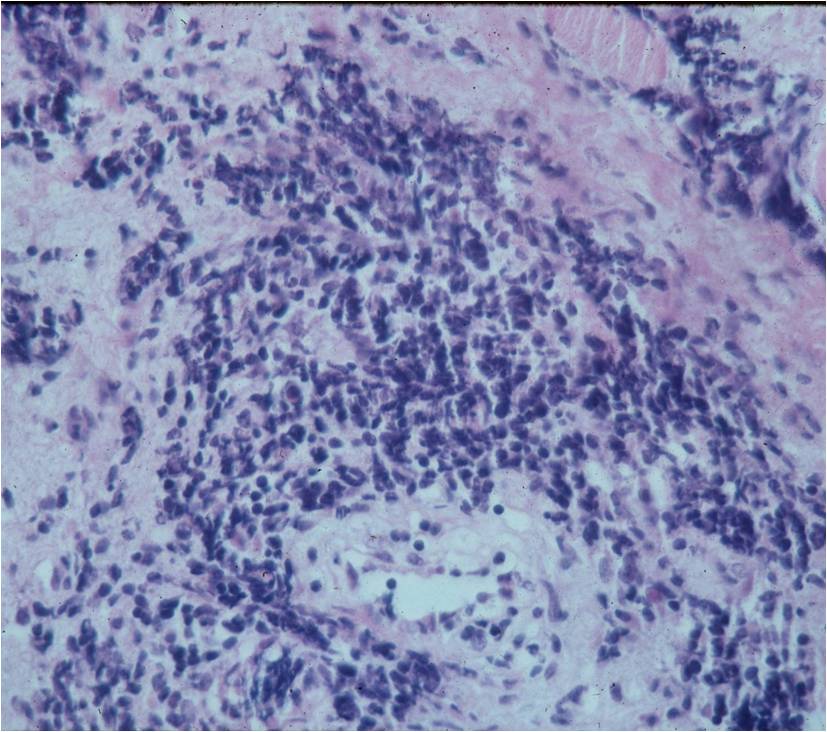

Microscopic Pathology

- Diffuse growth pattern

- Mixture of small lymphocytic cells and larger histiocytic components (Large Malignant B Cells in most cases)

- Cells and no matrix

- Nuclei

- Vary in shape and size

- Grooved vesicular nuclei

- Prominant nucleoli

- Cytoplasmic glycogen is absent

- Complex reticulin framework

- Prominent fibroblastic component

- CD5 and Leukocyte Common Antigen Positive

- CD3+ and CD45+ for B Cell Lymphoma; CD3+ for Rare T-Cell